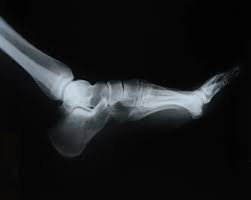

피로 골절이 자주 생기는 부위

피로 골절은 반복적으로 체중이 실리는 부위에서 흔히 발생합니다. 특히 아래 부위는 비교적 자주 언급됩니다.

• 발등과 발바닥 앞쪽

• 정강이 뼈 주변

• 발목과 뒤꿈치 근처

• 장시간 서 있거나 걷는 경우 무릎 아래 부위

러닝이나 등산을 갑자기 시작했거나, 평소보다 활동량이 급격히 늘어난 경우, 또는 딱딱한 바닥에서 오래 서 있는 생활이 이어졌다면 위험이 커질 수 있습니다.